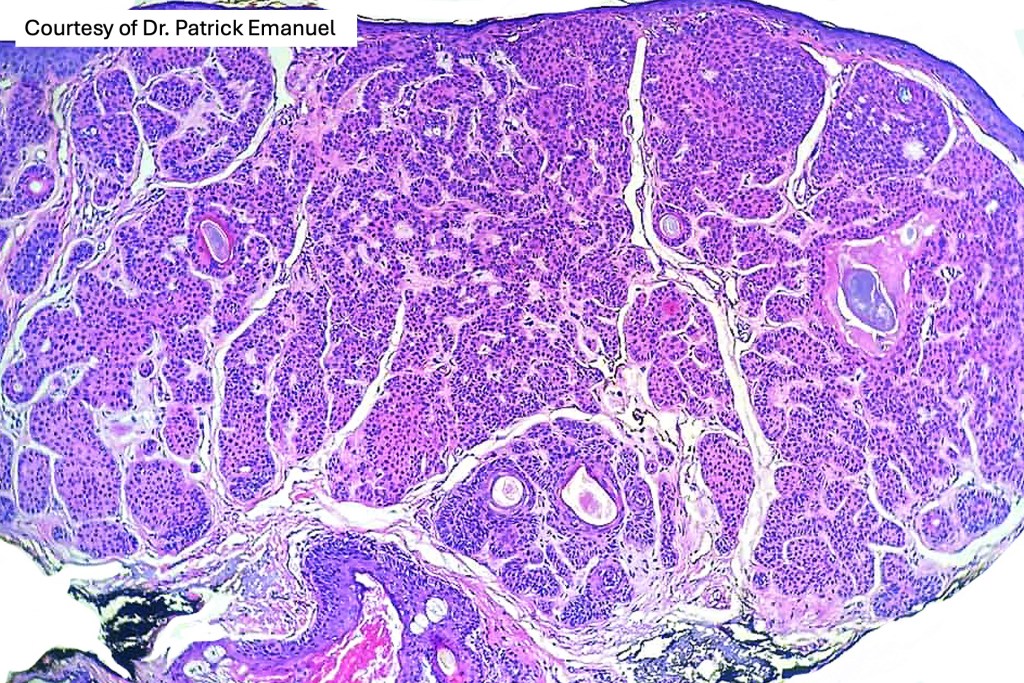

•Vertically orientated, folliculocentric, thin, anastomosing strands composed of basaloid cells embedded in a loose fibrous stroma

•Variable keratocysts

•No retraction artifact or stromal mucin deposition